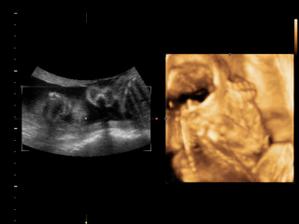

23.8.2010 první UTZ v ČR. Byli jsme zrovna 11tt+5 ale mrňousek odpovídal velikosti 12tt+1. NT Sreening dopadnul dobře a my jsme dostali první fotečky.

18.10.2010 Naše prďolka se konečně otočil a ukázel se. Pán doktor nám potvrdil,že to bude chlapeček. Nemůžeme si vybrat jméno. Pro holčičku bylo jasné,ale u chlapečka máme problém. Seznam se zůžil na 3 jména. Martin,Daniel a nebo Domink.

14.12.2010 (27tt+6)Nám pan doktor řekl,že Daneček je ukázkový, že má 1,076kg a má vše co má mít! 🙂

11.1.2011 (31+6) Tak Deneček má už 2kg. Dostali jsme železo,jelikož máme trochu nízký krevní obraz,ale to je normálka.

7.2.2011 přesně týden po návštěvě pohotovosti. Měla jsem akutní infekci horních cest dýchacích. Projistotu mně poslali i na gynekologii,kde bylo vše v pořádku,akorát jsme měli rychlejší ozvy,ale to bylo horečkou. Dr. nám řekla,že daneček má cca 3kg. Dneska na poradně (35+5) nám pan Dr. řekl 2705g,takže to bude asi +-3kg. Další poradnu máme za týden a to půjdeme na stěry kvůli streptokoka.

14.2. (36+5) Vše je vpořádku, spousta vody placenta taky ok, Daneček je nachystaný a podle utz tabulky má 2908g. Odebrány stěry na streptokoka. Příští týden budou vysledky.

21.2.2011 (37+5) Všechno je stále perfektní. Streptokok negativní a Daneček má 3,1kg 🙂

28.2.2011 (38+5) 3,25kg Dostali jsme žádanku do porodnice na převzetí péče,takže pozítří se jdeme přihlásit do Vítkovické porodnice.